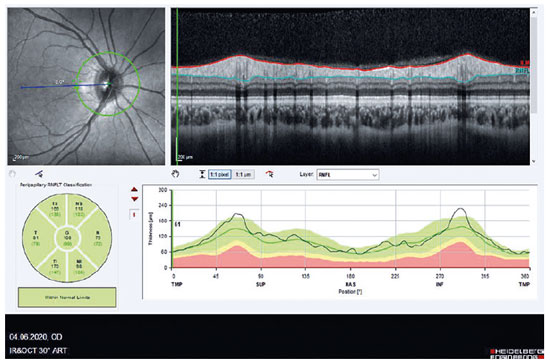

We evaluated the effect of COVID-19 infection on the peripapillary retinal nerve fiber layer (pRNFL) using spectral-domain optical coherence tomography (SD-OCT) (Figure 1). Our study had been approved by the institutional review board and was performed in accordance with the tenets of the Declaration of Helsinki.

A total of 32 eyes from 32 patients with COVID-19 (Group 1) and 34 eyes from 34 healthy subjects (Group 2) were included. All patients in Group 1 were positive for COVID-19 following real-time reverse transcriptase-polymerase chain reaction from nasopharyngeal swabs. No significant difference in age and gender had been observed between both groups (p=0.6 and 0.4, respectively), while slit-lamp examination was normal for all cases. The average pRNFL thickness values are presented in t able 1. Accordingly, a significant difference in the inferonasal sector had been observed between both groups (p=0.04).

The RNFL of the retina contains the non-myelinated axons of retinal ganglion cells that form the optic nerve. Depending on the physiological parameters of RNFL, localized defects are usually more frequent in the temporal inferior fundus region and temporal superior region. Our study found a significant thinning in the inferonasal sector in patients with COVID-19. However, none of patients had coexisting retinopathy or optic nerve changes and a history of optic neuropathy or glaucoma.

Our findings suggest that subclinical damage may occur in patients with COVID-19, which may be localized rather than diffuse axonal loss. To best of our knowledge, this has been the first study to compare pRNFL thickness between patients with COVID-19 and healthy controls. As such, localized RNFL defects that can be assessed by noninvasive SD-OCT imaging may be added to the retinal features of COVID-19.